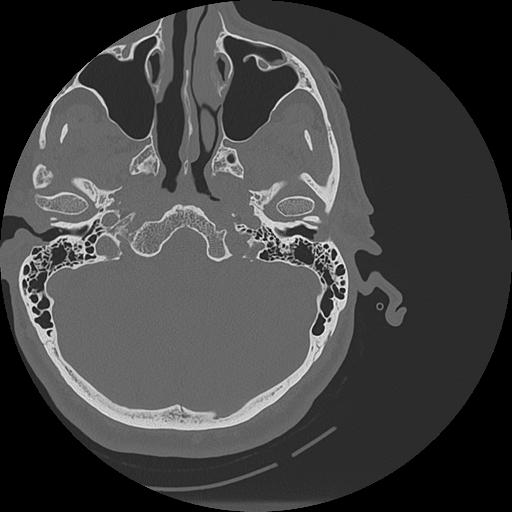

7 HUESO,,Vol,0.5,HUESO,,